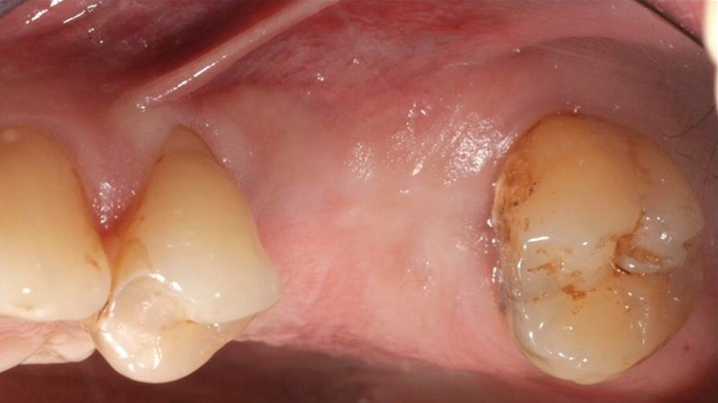

Klinikinis atvejis: Vėlyvoji implantacija: viršutinio žandikaulio ančio dugno elevacija, implanto sriegimas ir kraštinė kaulo regeneracija;

- Dr. Irfan Abas klinikinis atvejis -

Vėlyvoji implantacija, ančio dugno elevacija, ančio dugno elevacija atviru būdu, kraštinė kaulo regeneracija, Dr. Irfan Abas, AnyRidge, MiLA chirurginis rinkinys, kaulo regeneracija;